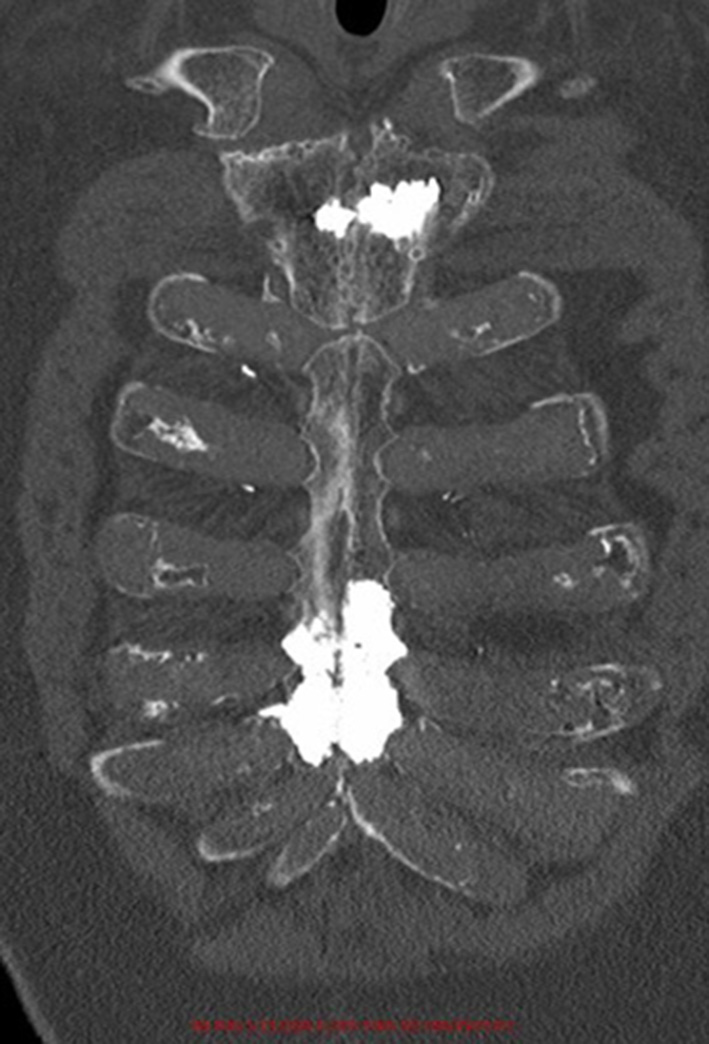

Figure 3

Post-operative coronal computed-tomography image of patient 1.

Cementoplasty Procedures

The procedure time was 27 ± 12 minutes. The radiation exposure was 0.13 ± 0.04 mGy. During the procedure, 3 ± 3 mL of cement were injected. Figures 1–4 depict example of pre- and postinterventional CT findings.